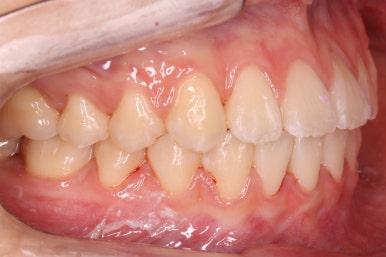

부산교정 키다리아저씨치과에 처음 내원하셨을 때의 입안 모습입니다.

윗니가 삐뚤어져 있고, 아래앞니 사이에는 틈이 듬성듬성 보입니다.

아랫니를 살펴보면 화살표 표시를 해둔 송곳니~송곳니 사이에 치아가 1개 모자랍니다. 원래는 4개의 앞니가 있어야 하는데, 3개 밖에 없었습니다. 이런 결손치아의 경우는 다음과 같은 문제가 생깁니다.

결손치아 부위에 틈이 생깁니다.

결손치아 주위 치아들이 제대로 서있지 못하고 기울어지게 됩니다.

위-아래 짝이 맞지 않아 중앙선이라든지 교합에 문제가 생깁니다.

이번의 경우 앞니가 하나 없는 경우여서 위-아래 앞니가 앞뒤로 간격이 멀어지게 됩니다.